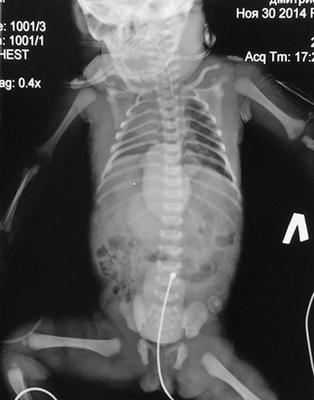

Доношенная девочка переведена в отделение анестезиологии и реанимации кардиохирургии перинатального центра ГБОУ ВО «СПбГПМУ» на 2-е сутки после рождения в Демьянской ЦРБ. В анамнезе: ребенок от вторых срочных самостоятельных родов, ручное отделение последа, седьмой беременности, во время беременности мать на учете не состояла, простудные заболевания в анамнезе. Масса ребенка при рождении 2215 г, рост 44 см. Апгар 7/8 баллов, состояние с рождения тяжелое, неврологическая симптоматика проявлялась гипотонией, гипорефлексией, акроцианозом. С 1-х суток жизни ребенок находился на искусственной вентиляции легких (ИВЛ), с жесткими параметрами, показатели сатурации 95 %. В легких дыхание проводилось с обеих сторон с наличием единичных хрипов проводного характера. Тоны сердца ритмичные. ЧСС — 130/мин. АД 52/25 мм рт. ст. Живот не вздут, мягкий, диурез сохранен. Локально определялся дефект передней грудной и брюшной стенок, в просвете дефекта зияло сердце с омфалоцеле (содержащим, предположительно, желудок), непокрытые кожно-апоневротическим компонентом. Дефект был прикрыт марлевой повязкой, смоченной в подогретом растворе фурацилина. В Демьянской ЦРБ получала лечение: антибиотики ампициллин 50мг/кг 2 раза/сутки внутривенно, инфузионная терапия (глюкоза 10 %, аминовен 10 %) в V = ФП, дицинон, обезболивающие, инотропная поддержка (дофамин 0,5 % 2мкг/кг × мин).

При осмотре новорожденной на момент поступления в кардиохирургического отделения перинатального центра ГБОУ ВО СПбГПМУ выявлены все 5 признаков синдрома, в том числе врожденный порок сердца, заболевание классифицировано как 1-й класс по Тояма (рис. 1).

Рис. 1. Новорожденная девочка, 2-х суток жизни, поступившая с диагнозом врожденная эктопия сердца, омфалоцеле

Ребенок был осмотрен коллегией специалистов: неонатологом, кардиологом, кардиохирургом, торакоабдоминальным хирургом, неврологом. Состояние ребенка расценено как стабильное, тяжелое, сознание на момент осмотра медикаментозно угнетено. При поступлении пациентке выполнена обзорная рентгенограмма грудной и брюшной полостей, визуализирующая сердечную тень в проекции эпигастрия, что дало представление о эвентрации сердца на переднюю брюшную стенку, однако не отражало анатомию внутрисердечных структур. Верхняя доля правого легкого ателектазирована, в дистальных отделах обоих легких выявлены признаки интерстициального отека легочной паренхимы. Контуры диафрагмы четкие, ровные (рис. 2). Учитывая отсутствие возможности проведения трансторакального ЭХО-КГ, в силу отсутствия кожно-апоневротического компонента, покрывающего сердце, в рамках предоперационного планирования принято решение о выполнении мультиспиральной компьютерной томографии (МСКТ) области грудной клетки с целью определения анатомии внутрисердечных структур и определения типа врожденного порока сердца.

Рис. 2. Обзорный ренгтеновский снимок, показывающий атипичную локализацию сердечной тени, асимметричное положение диафрагмы, неравномерную пневматизацию легочной ткани